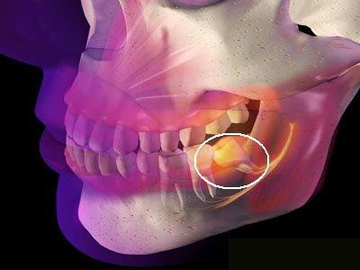

2、手術復雜性:拔智齒手術的復雜性也會影響費用,如果智齒生長位置正常,手術相對簡單;如果智齒被埋在骨頭里,需要切開牙齦和骨頭,手術難度增大,費用相應增加。

1、術前檢查:拔智齒前需要進行口腔檢查、X光片等檢查,以了解智齒的位置和周圍結構,這些檢查費用也是拔智齒總費用的一部分。